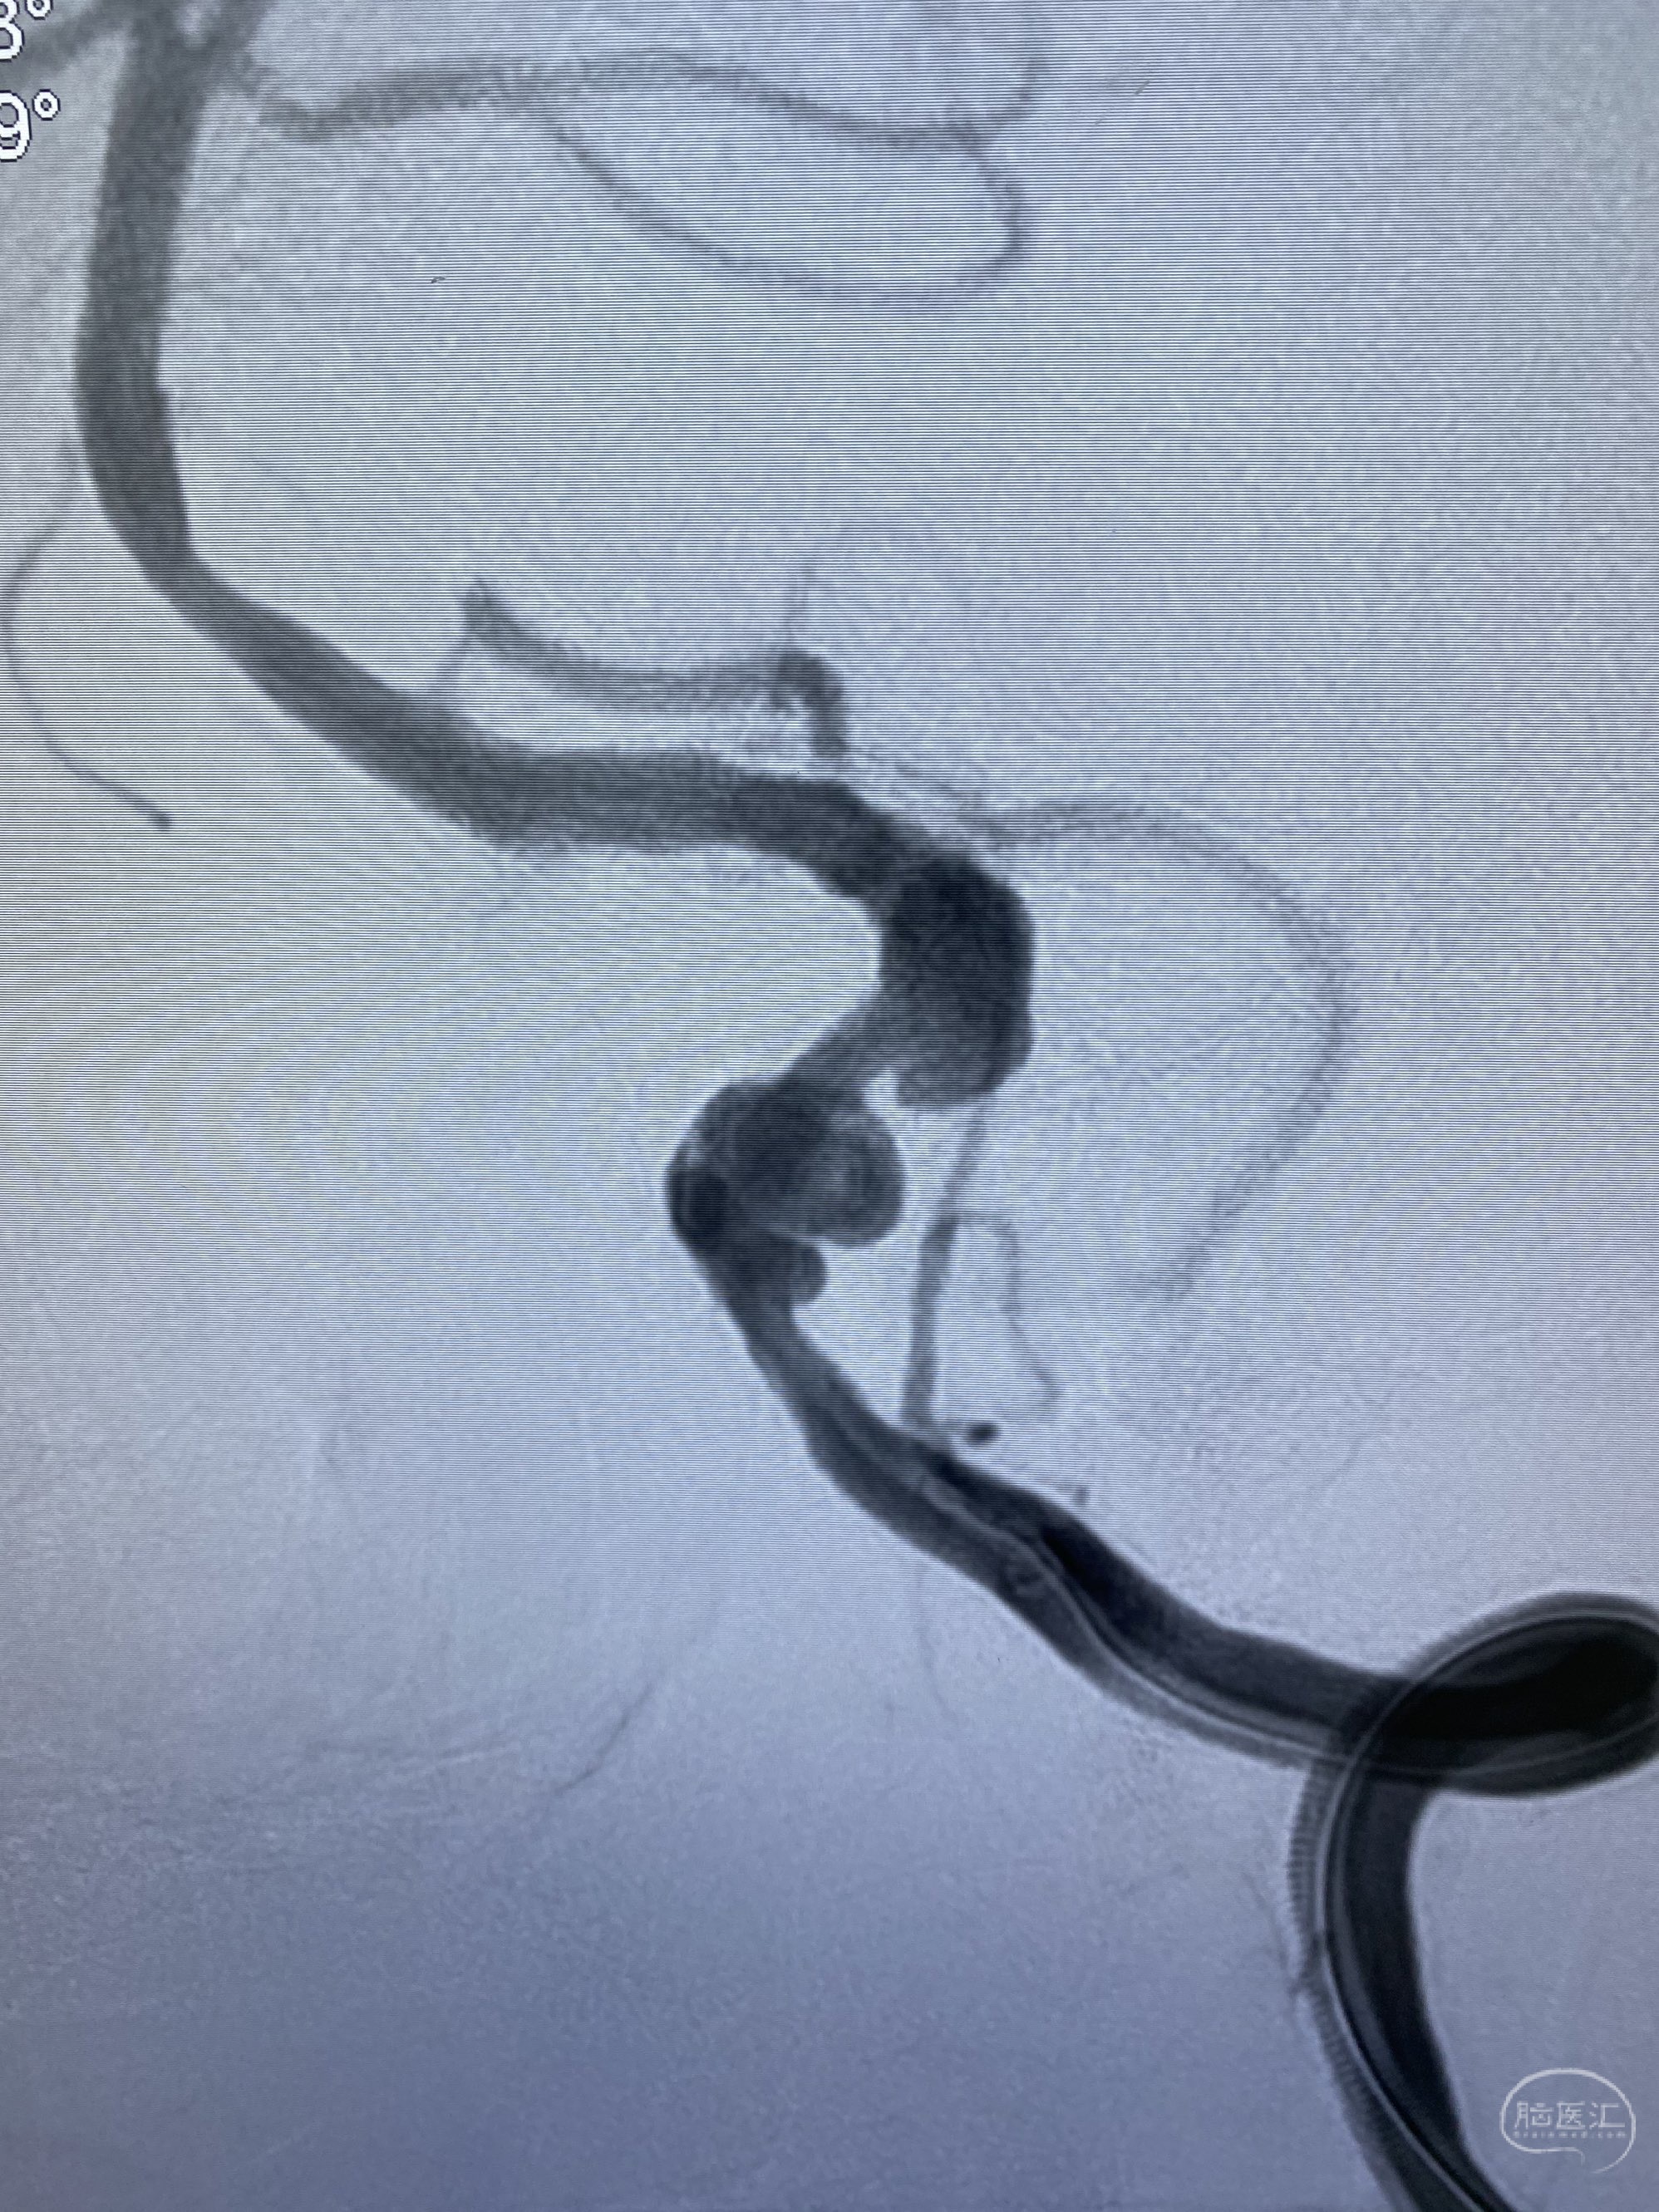

今日手术,TJG,M62Y,一期左侧颈动脉狭窄支架植入,二期椎动脉V4段多发夹层动脉瘤伴狭窄,常规支架辅助栓塞方法复杂又危险,血流导向装置植入快捷又安全。南阳市中心医院神经内科脑血管病介入团队pipeline flexFD植入两人导师资格。

椎动脉颅内段多发夹层动脉瘤伴载瘤动脉狭窄pipeline flex植入

今日手术,TJG,M62Y,一期左侧颈动脉狭窄支架植入,二期椎动脉V4段多发夹层动脉瘤伴狭窄,常规支架辅助栓塞方法复杂又危险,血流导向装置植入快捷又安全。南阳市中心医院神经内科脑血管病介入团队pipeline flexFD植入两人导师资格。